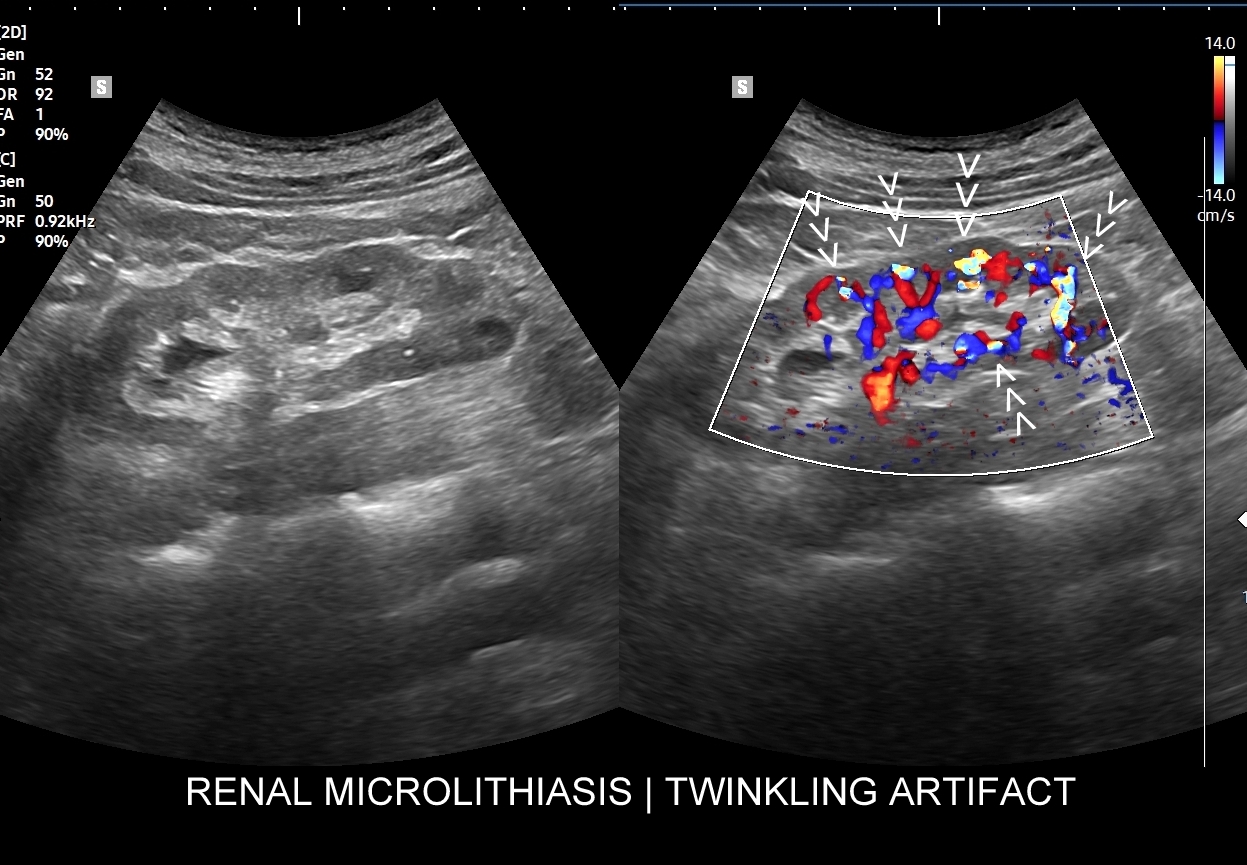

Ważnym trybem pomocniczym jest color-Doppler, w którym to trybie uzyskuje się tzw. artefakt migotania, często nawet na bardzo drobnych złogach niewidocznych w trybie B. Uzyskanie efektu migotania jest niestety zależne o jakości aparatury USG, a także od ustawień Dopplera i software’u.